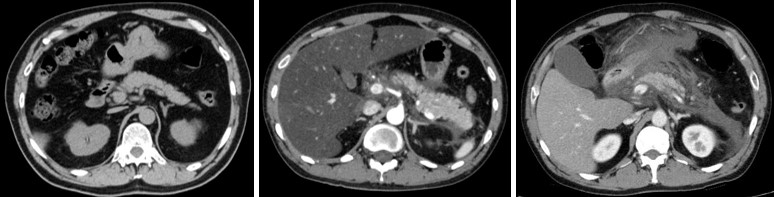

さらに、LRRK2の機能を活性化させた膵炎モデルマウスを用いて、腸管内の細菌・真菌をそれぞれ除去した場合の症状を比較したところ、真菌を除去した場合にのみ重症化が顕著に抑制されることが分かりました。この結果から、膵臓が真菌に感染した場合、特に急性膵炎が重症化する可能性が示唆されました。また、LRRK2が活性化しているモデルマウスの膵臓では、細菌ではなく真菌の成分に反応して免疫反応が起こることも明らかになりました。

以上の結果から、膵臓に真菌が感染した際にLRRK2が活性化され、急性膵炎が重症化することが明らかになりました。本研究成果により、真菌感染を介して活性化されるLRRK2を標的とした、重症急性膵炎の新たな治療法の確立が期待されます。

さらに、急性膵炎の重症化に、細菌と真菌のどちらがより影響するか検証するため、腸管内の細菌と真菌をそれぞれ抗細菌薬と抗真菌薬で除去し、症状の変化を確認しました。その結果、抗細菌薬による細菌の除去はLRRK2 Tgマウスの膵炎の重症度に影響を与えず、抗真菌薬による真菌の除去により、膵炎は著しく軽症化しました。さらに、重症膵炎を発症したLRRK2 Tgマウスの膵臓のマクロファージ・樹状細胞は、細菌成分ではなく真菌成分に反応し、炎症性サイトカインを多く産生しました。

最後に、腸管の真菌叢の違いにより、LRRK2の機能が変化し、膵炎の重症化に影響しているかどうかを検討しました。次世代シークエンス解析により、野生型マウスとLRRK2 Tgマウスの真菌叢を網羅的に解析した結果、常在真菌叢のレベルでは大きな違いはなく、真菌叢の違いは重症化に影響しない可能性が高いことが明らかになりました。

重症急性膵炎には真菌感染が高い確率で起こり、真菌に対する免疫反応が重症化に大きな影響を及ぼすことが臨床的に知られていますが、これまではメカニズムが不明で、重症急性膵炎の治療法は確立されていませんでした。本研究成果により、LRRK2を標的とした重症膵炎の予防・治療法の確立が期待されます。